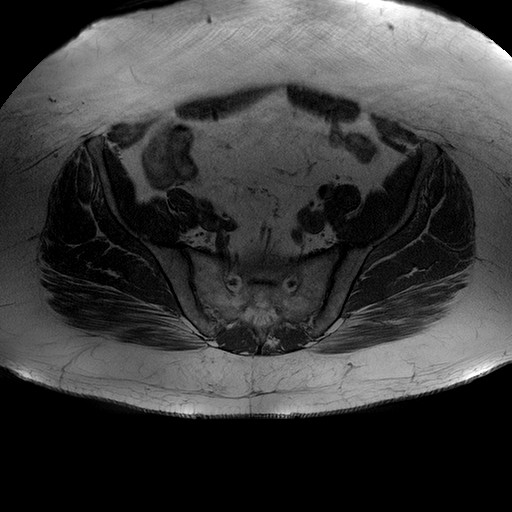

Esami: RMN BACINO

Evidenti e simmetriche alterazioni osteofitosiche in regione coxo femorale con riduzione delle rime articolari. Degenerazione completa del cercine glenoideo. Non attuali segni di versamento articolare. Non segni di edema osseo che escludono attuale algodistrofia od osteonecrosi. Lieve e simmetrica riduzione del trofismo della muscolatura glutea.